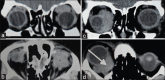

Purpose: The objective is to analyze the radiological diagnosis of orbital lesions and their correlation with the final histopathological findings. We compared the initial reports by extramural radiologists and an in-house radiologist specialized in orbital imaging to evaluate the diagnostic accuracy in the interpretation of orbital imaging.

Methods: This was a retrospective chart review of forty patients referred to a Tertiary Eye Care Center in South India over a period of 7 years. These patients already had their imaging done elsewhere. The imaging was re-evaluated by an in-house radiologist. The radiological findings were correlated with the histopathological diagnosis. The diagnostic accuracy between the two radiologists was compared. The sensitivity, specificity, positive predictive value (PPV), and negative predictive value in differentiating malignant from benign lesions were calculated in both groups. The sensitivity and PPV of the radiological diagnosis for neoplastic and inflammatory lesions in both groups were analyzed.

Results: The accuracy in differentiating malignant from benign and inflammatory lesions by our in-house radiologist and extramural radiologists was 95% (κ = 0.9 [0.764, 0.997]) and 50% (κ = 0.036 [-0.160, 0.232]), respectively. The sensitivity and PPV of the radiological diagnosis by our in-house radiologist were 93.31% and 100% for benign lesions and 95.24% and 95.24% for malignant lesions. On the contrary, reports from the extramural radiologists showed a sensitivity and PPV of 76.92% and 66.67% for benign lesions and 14.28% and 60% for malignant lesions.

Conclusion: A high radiological diagnostic accuracy is possible when analyzed by radiologists experienced in orbital imaging.